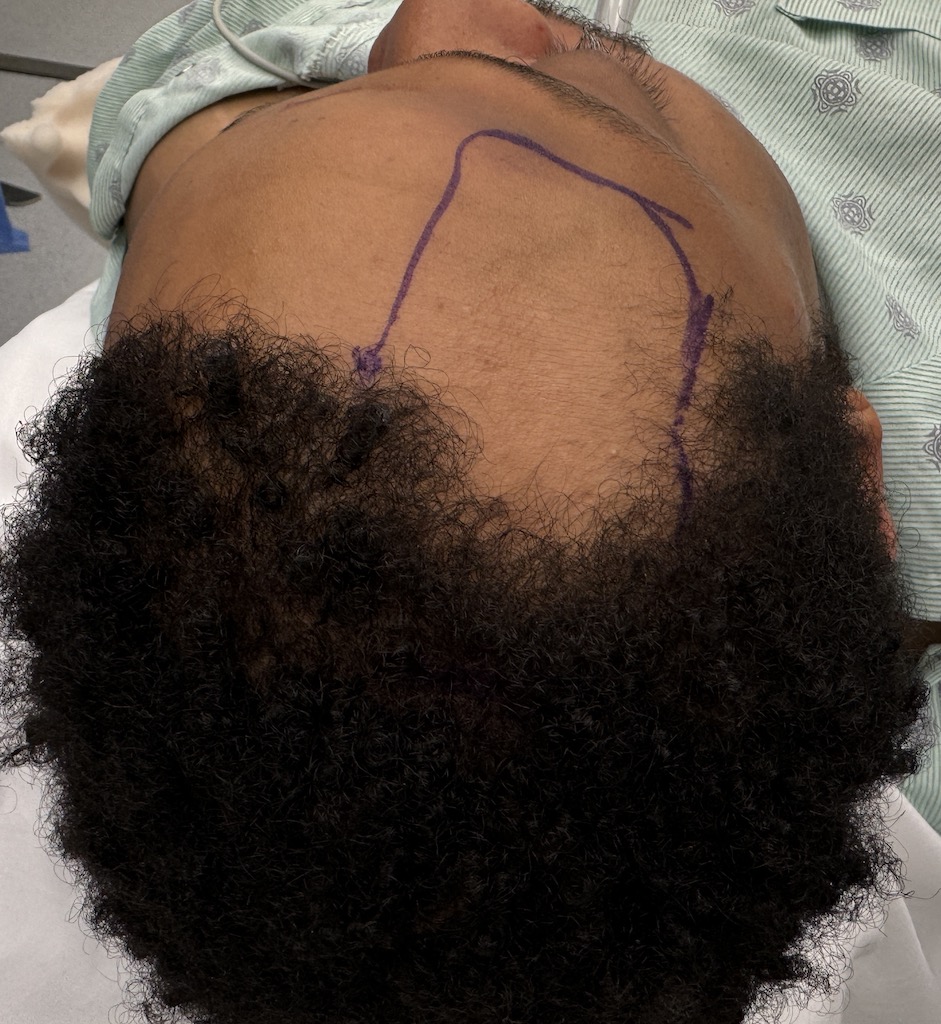

Reconstruction of loss of frontotemporal craniotomy bone flap from neurosurgery.

Reconstruction of full-thickness skull defect with computer-generated HTR-PMI cranial implant.

Reconstruction of loss of frontotemporal craniotomy bone flap from neurosurgery.

Reconstruction of full-thickness skull defect with computer-generated HTR-PMI cranial implant.